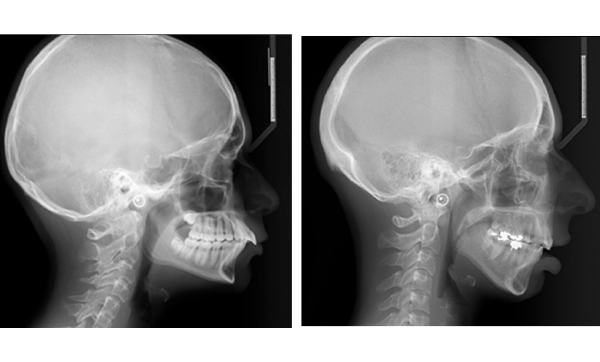

– ceux qui savent et sont conscients que la chirurgie est la seule alternative à leurs problèmes esthétiques (fig. 1) ;

– ceux qui s’y attendent plus ou moins mais ont besoin d’une confirmation de leurs problèmes par l’orthodontiste (fig. 2) ;

– ceux qui n’en sont pas du tout conscients, mais dont la chirurgie reste la seule solution à leurs problèmes (fig. 3).